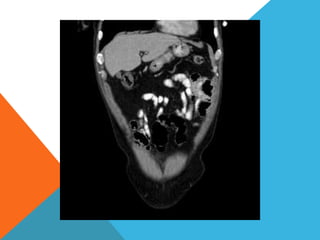

El paciente presentó síntomas de sangrado digestivo y pérdida de peso. Exámenes revelaron gastritis crónica asociada a H. pylori. Un tumor fue descubierto en una colonoscopia normal. La cirugía removió un tumor fibroide solitario, una rara neoplasia mesenquimal que usualmente crece lento y tiene bajo potencial de malignidad. El pronóstico después de la remoción quirúrgica es generalmente bueno.